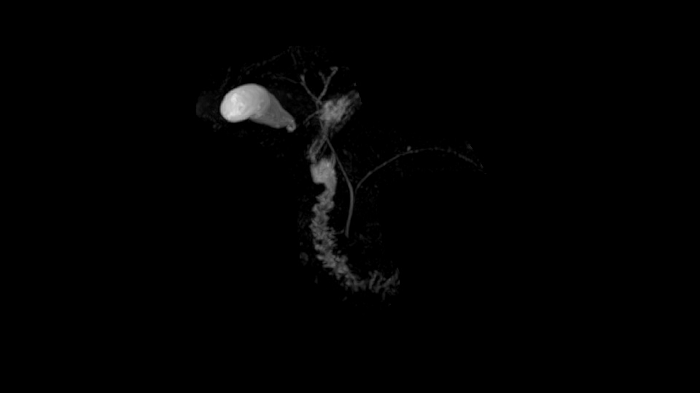

Time-of-flight angiography

Non-contrast enhanced angiography of the cranial vessels is used to detect vessel occlusions or aneurysms. High-resolution ToF angiography can also show small arteries for subtle diagnoses.

Image Courtesy: University Hospital Erlangen, Germany | Image-ID: 4aaaa0466